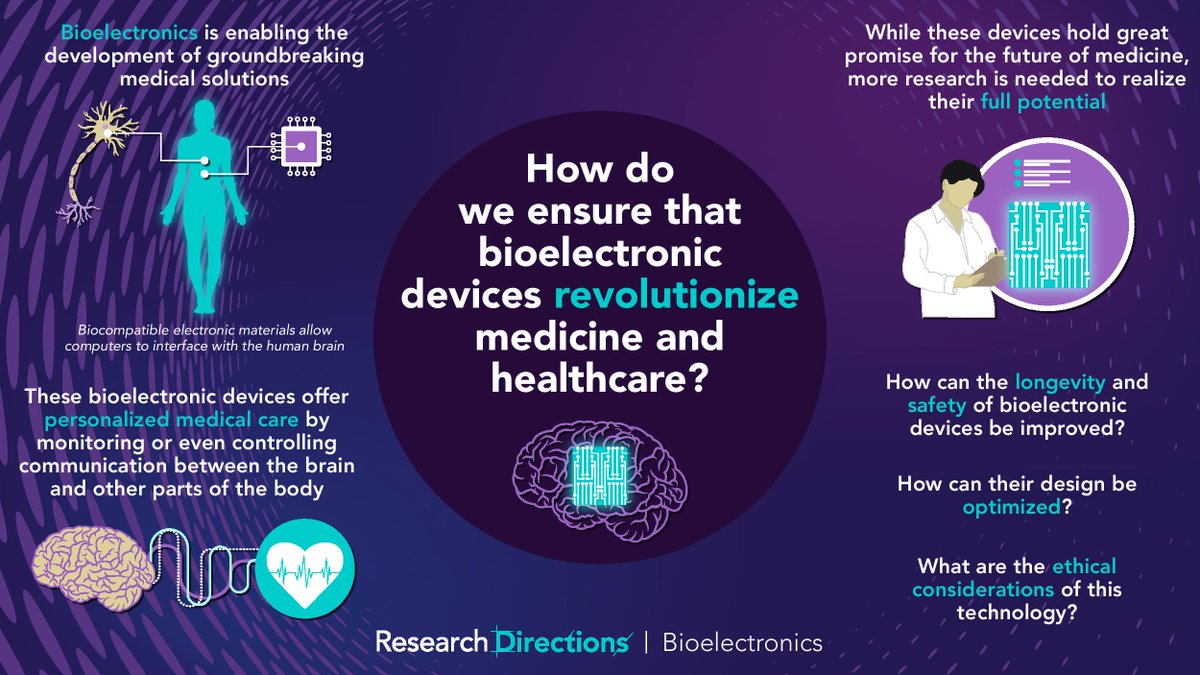

#RDBioelectronics welcomes contributions from researchers to answer this question from @sc_laboratories: 🟣How do we ensure that #bioelectronic devices revolutionize medicine and healthcare? Learn more about this question and how to contribute:cup.org/3pcKJ4o #bionics